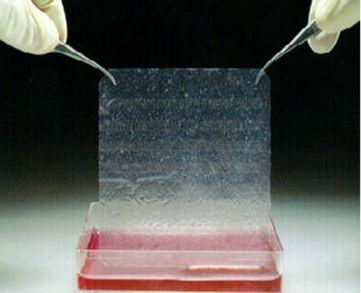

STANFORD – E’ stata realizzata la prima ‘pelle artificiale’ che e’ sensibile al tatto e puo’ ‘auto-guarire’ quando subisce un taglio o